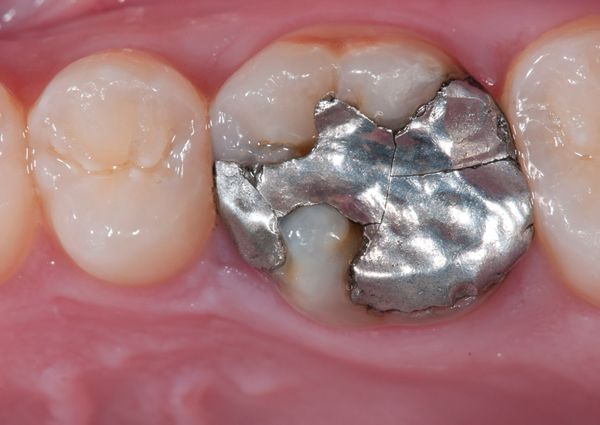

Fig 17. Two-molar full-crown porcelain-fused-to-metal restoration made with a CL-IV substrate.

Figure 17

CL-IV (Metal Ceramics)

CL-IV represents metal ceramics, which are essentially CL-I materials fused to a highly supportive substrate metal, allowing their use in high-stress clinical situations where conventional crowns and esthetics may be required. They are ideal when minimal-to-no tooth structure remains.

Like CL-III materials, CL-IV metal ceramics demonstrate greater strength but limited esthetic characteristics. CL-IV metal ceramics require a thickness of at least 1.5 mm to create lifelike esthetics.29 These metal ceramics demonstrate similar qualities to CL-III zirconia-based restorations,30 but the metal substructures do not have the same thermal firing sensitivity as zirconia.31

CL-IV metal ceramics can be improved in esthetic qualities with use of a much higher gold framework material (eg, Captek™, Argen USA Inc., www.captek.com) (Figure 17).